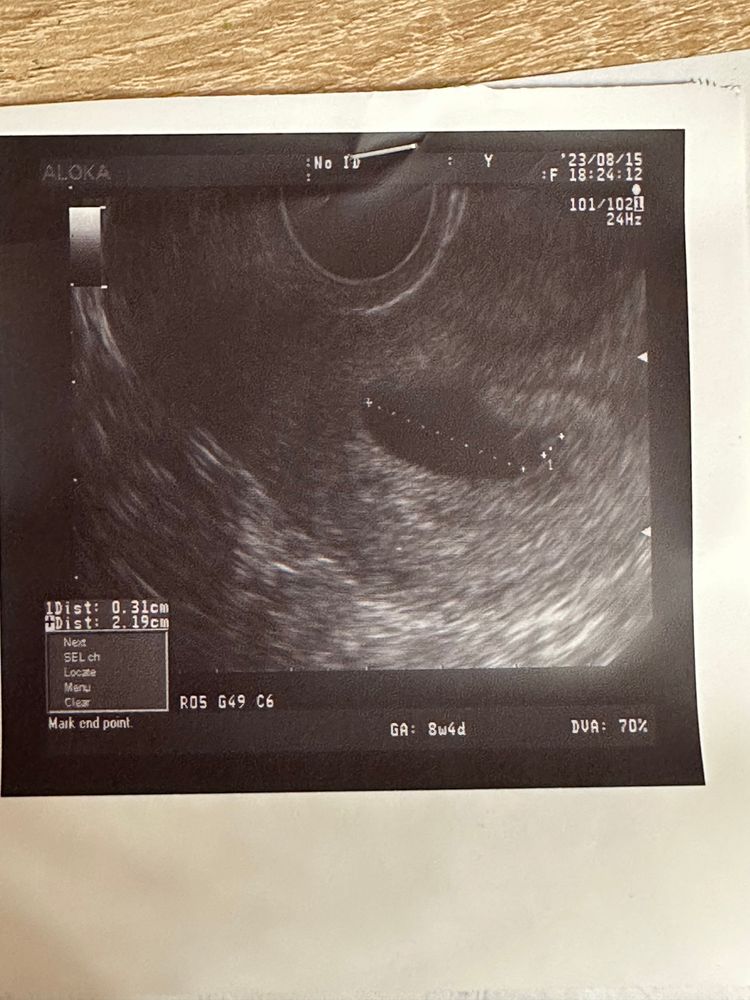

ПЯ большое 17мм ,ктр-3 мм, жм-5

Тоесть у вас сейчас девятая неделя? И такие показатели? Вы же понимаете что на этом сроке эмбрион должен быть не 3мм, а 3 см. А у вас что пя, что ктр на 4 недели ((((.

Ксеня, я не хочу вас расстраивать но 90% того что беременность замерла недели 4 назад. Судя по размерам пя и ктр Либо у вас была супер поздняя овуляция. И срок у вас по этому на 4 недели отличается. Но, вы говорите были 3 недели назад на узи? И что там было? Уже было пя? Если да, то к сожалению даже на позднюю овуляцию спехнуть нельзя Мне очень жаль. Но, лучше не затягивайте. Переделайте узи через 3-4 дня.

Ксеня, а примерно когда овуляция была? И цикл обычно у вас сколько дней? Просто если 25.07 было на 3 недели, то сейчас должно быть шесть. На 6 недели эмбрион примерно 5-8 мм и чсс 120 минимум. А у вас получается пя соответствует 6 недели, а эмбрион на 5. При этом у вас по месячным почти 9. Ну слишком большая разница, ну правда.

Ксеня, ну хотя-бы на 6-7 недель должен быть эмбрион сейчас развит у вас, даже учитывая вашу овуляцию. ((( ЧСС обязательно должен быть на вашем сроке. Если через 3-4 дня ничего не поменяется, ждать смысла дальше нет. Так и до воспаление можно дойти.

Размеры то нормальные, а вот сердце есть? При таком ктр должно быть точно

Ксеня, ну да, но уже должно быть, конечно. У меня услышали сб на 2.1 ктр не на самом новом оборудовании, 105 было. Неделю можно не ждать. Дня 3 достаточно

Ксеня, у вас 8 недель уже по месячным. Если верно написали. Нечего там особо выжидать, конечно. Идите через 3 дня...

У меня при пя 16,5мм, жм3,2мм, ктр 2,4 мм, сб было 120 уд. Так что нормальные размеры у вас